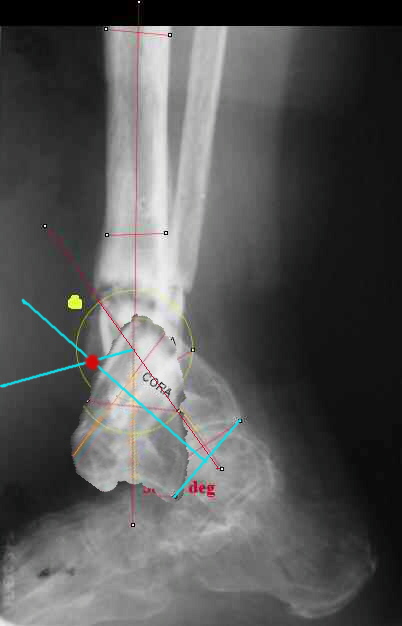

I played with your image using some orthopedic software we have been developing for digital

image analysis.

What you see marked up is the intercept of two mid-line tool centre lines, used to define the CORA. An angle tool gives the angular deformity and a circle tool is applied to show that a correction around the CORA through the old # will restore alignment without much translation.

Maybe my "embedded software" is obsolete but it hints me to place hinges at the yellow point - this must result with alignment and some lengthening without translation. What do you think?